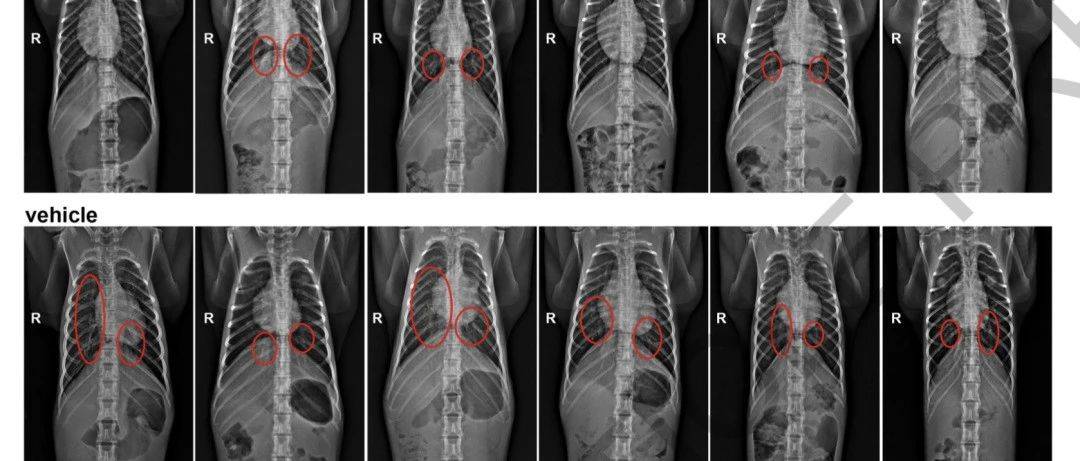

在接种疫苗3周后,研究人员对恒河猴进行SARS-CoV-2感染处理,并检测了其支气管肺泡灌洗液(BAL)和鼻拭子(NS)中的病毒RNA水平,发现与对照组中的高水平病毒RNA相比,疫苗接种组中病毒RNA水平显著降低,且其血浆中病毒RNA阴性,恒河猴仅表现出轻微的临床症状。

除此之外,研究人员还评估了对照和测试组中BAL和NS的亚基因组mRNA(sgmRNA)的水平,发现对照组的病毒载量在感染后4天达到峰值,而疫苗接种s抗体组中sgmRNA的水平明显降低。